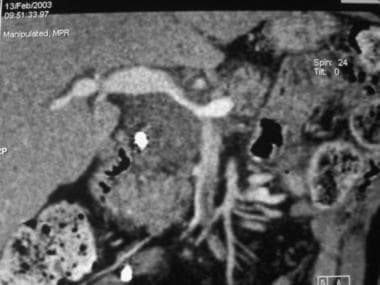

1. Imaging of Pancreatic Masses by Dr. Zainab Vora

In this super informative lecture, Dr. Zainab Vora discusses the core of imaging pancreatic masses in detail.

Key Highlights:

• Adenocarcinomas: The most common pancreatic mass in clinical practice.

• Cystic and Neuroendocrine Tumors: High-yield topics for exam

• Surgical Implications: Anatomy and Surgical decision-making in pancreas surgeries: Whipple’s procedure, distal pancreatectomy

• Cross-sectional Anatomy and Mastering the art of CT and Ultrasound imaging.